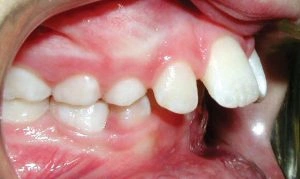

Upper Front Teeth Protrusion

The appearance and function of your teeth are impacted by this type of bite. It is characterized by the upper teeth extending too far forward or the lower teeth not extending far enough forward.